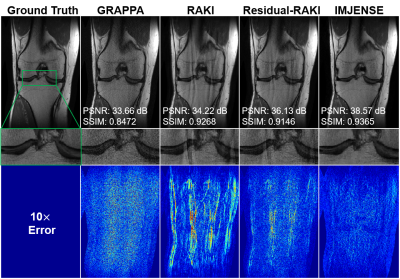

Figure 2 shows the results on the knee dataset with an acceleration rate of R=4 and 24 ACS lines. IMJENSE effectively removes the noise and aliasing artifacts that are severe on the reconstructed images by the compared methods, as illustrated by the zoomed-in images. Quantitatively, IMJENSE achieves the highest PSNR of 38.57 dB, more than 2 dB higher than Residual-RAKI, and the highest SSIM of 0.9365.

Figure 2. Comparisons of GRAPPA, RAKI, Residual-RAKI, and IMJENSE on the 15-channel knee dataset with 24 ACS lines at R=4. The zoomed-in images show that IMJENSE successfully removes the noise and artifacts. Quantitative evaluation metrics are reported below each image. IMJENSE achieves the highest PSNR and SSIM.